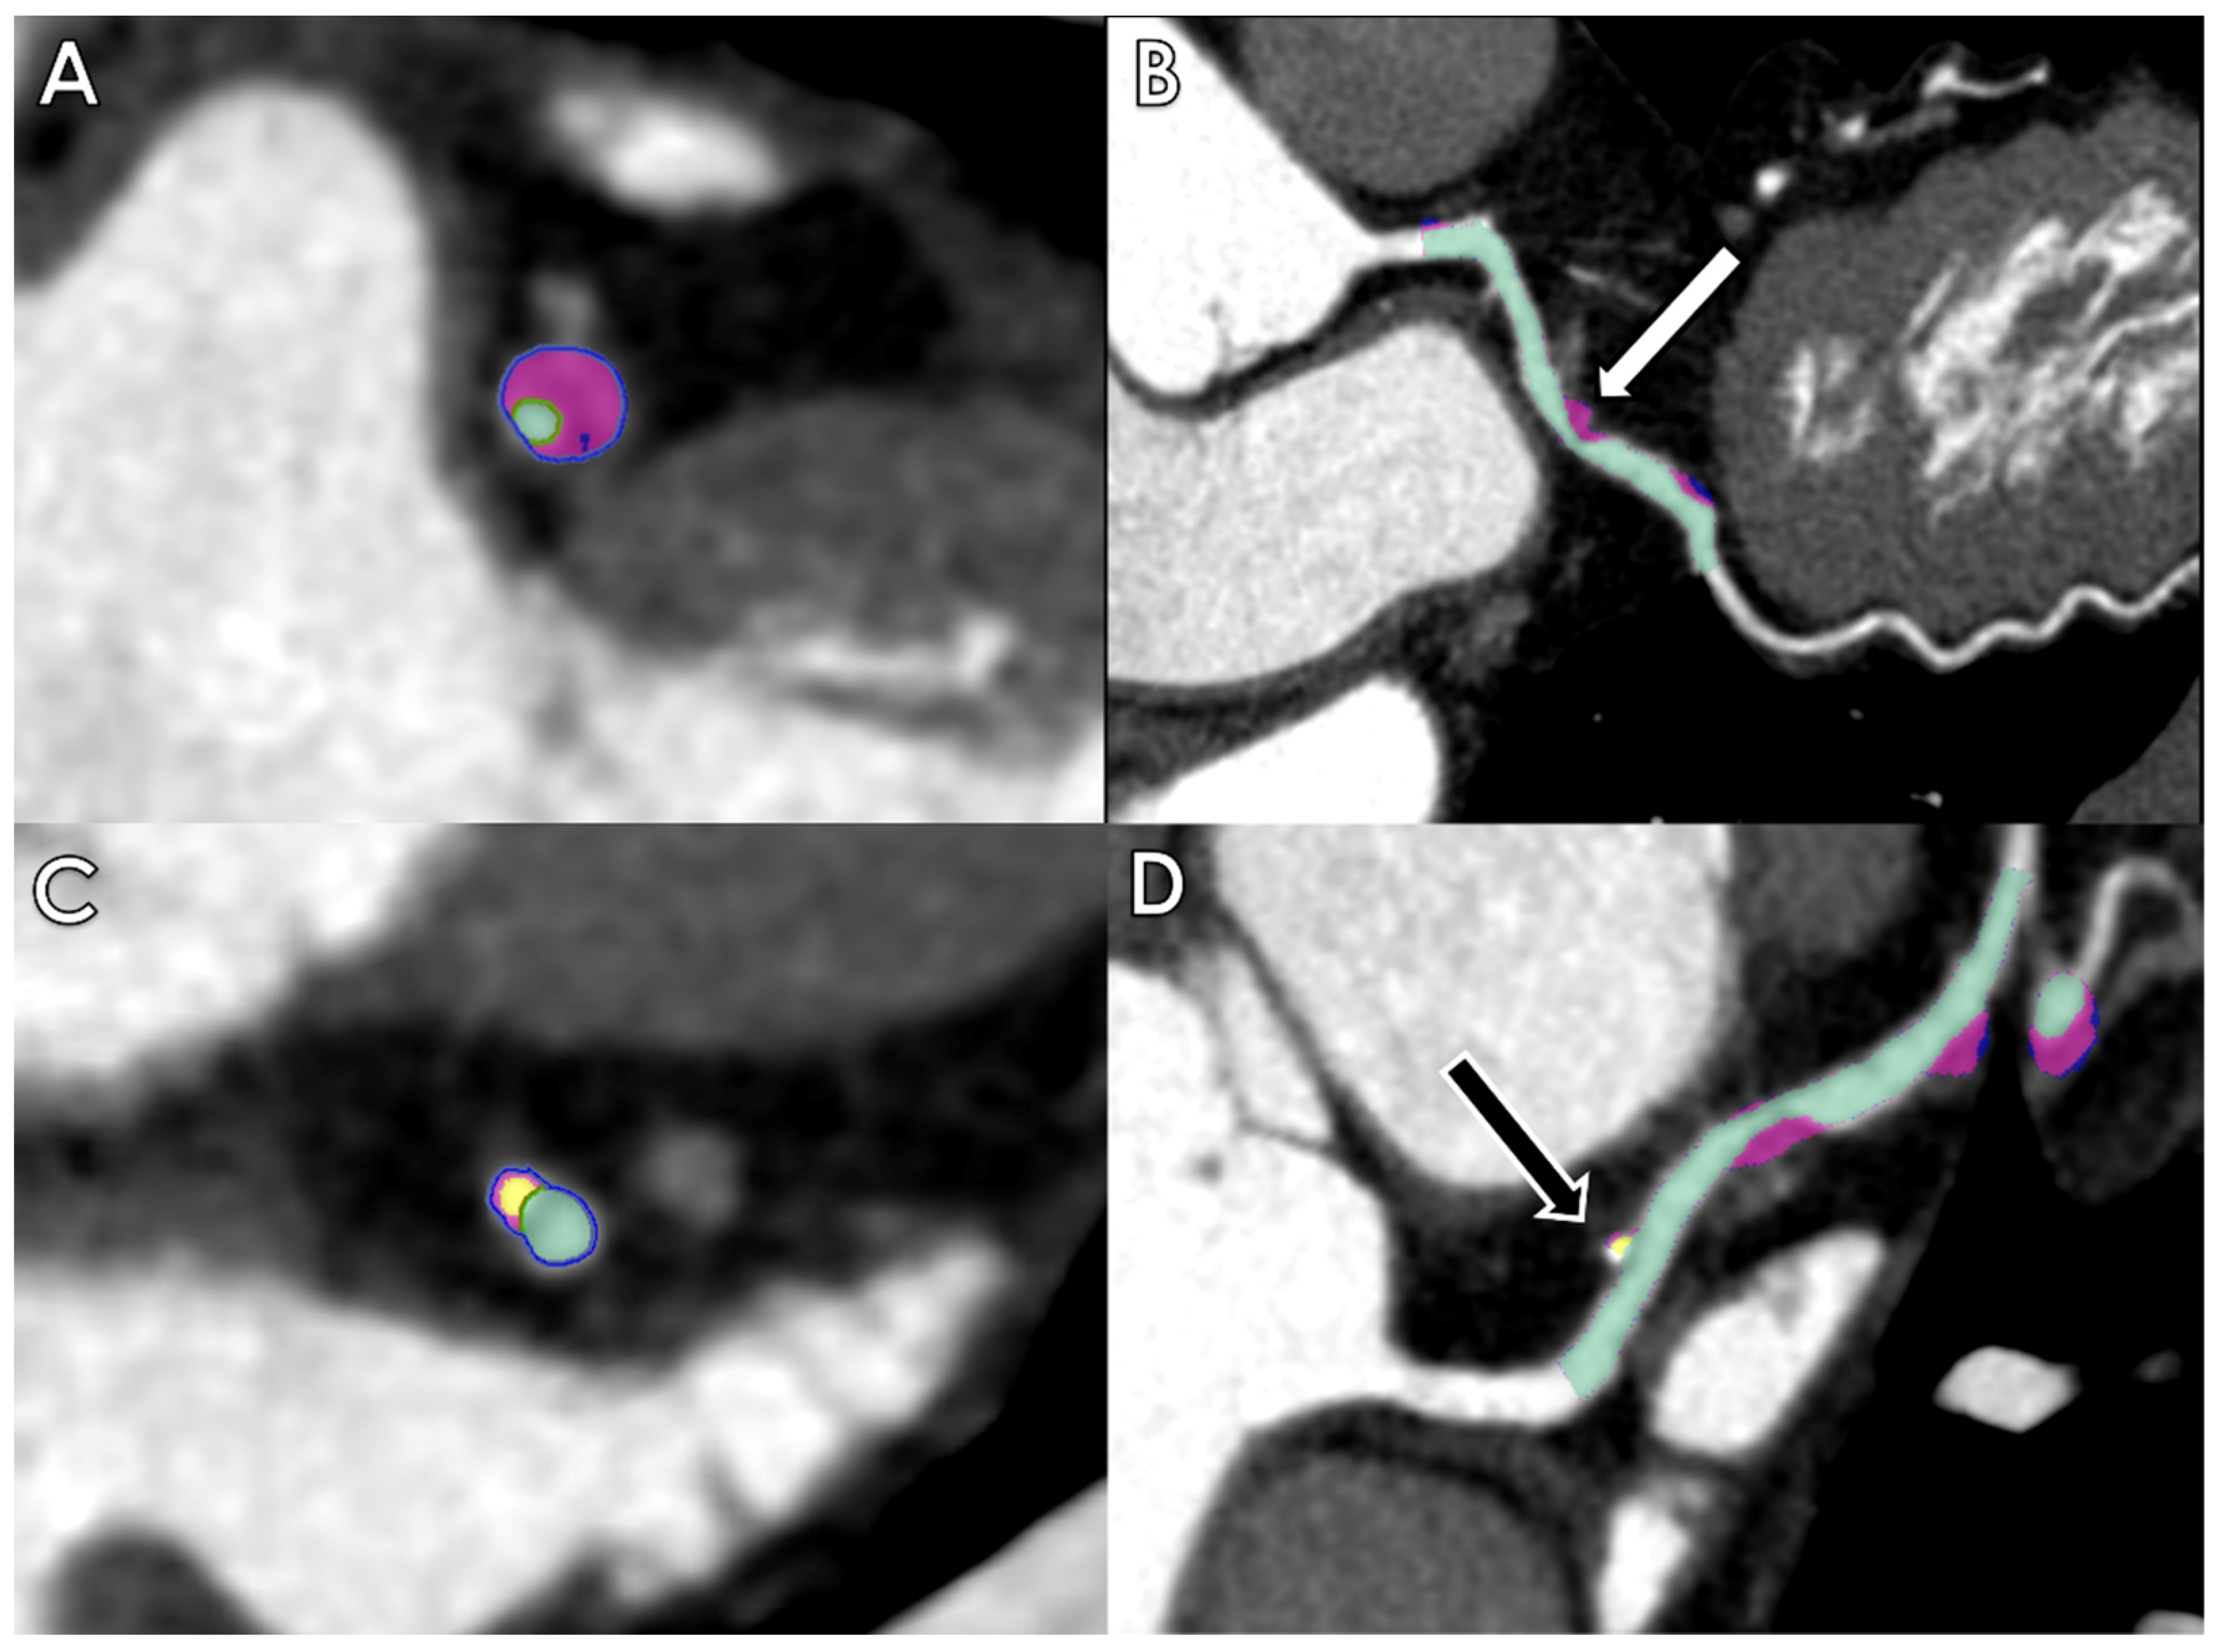

- Moccia, S.; Banali, R.; Martini, C.; Muscogiuri, G.; Pontone, G.; Pepi, M.; Caiani, E.G. Development and testing of a deep learning-based strategy for scar segmentation on CMR-LGE images. MAGMA 2019, 32, 187–195. [Google Scholar] [CrossRef]

- Zabihollahy, F.; Rajchl, M.; White, J.A.; Ukwatta, E. Fully automated segmentation of left ventricular scar from 3D late gadolinium enhancement magnetic resonance imaging using a cascaded multi-planar U-Net (CMPU-Net). Med. Phys. 2020, 47, 1645–1655. [Google Scholar] [CrossRef]

- Zhang, N.; Yang, G.; Gao, Z.; Xu, C.; Zhang, Y.; Shi, R.; Keegan, J.; Xu, L.; Zhang, H.; Fan, Z.; et al. Deep Learning for Diagnosis of Chronic Myocardial Infarction on Nonenhanced Cardiac Cine MRI. Radiology 2019, 291, 606–617. [Google Scholar] [CrossRef]

- Zhang, Q.; Burrage, M.K.; Shanmuganathan, M.; Gonzales, R.A.; Lukaschuk, E.; Thomas, K.E.; Mills, R.; Leal Pelado, J.; Nikolaidou, C.; Popescu, I.A.; et al. Artificial Intelligence for Contrast-Free MRI: Scar Assessment in Myocardial Infarction Using Deep Learning-Based Virtual Native Enhancement. Circulation 2022, 146, 1492–1503. [Google Scholar] [CrossRef]